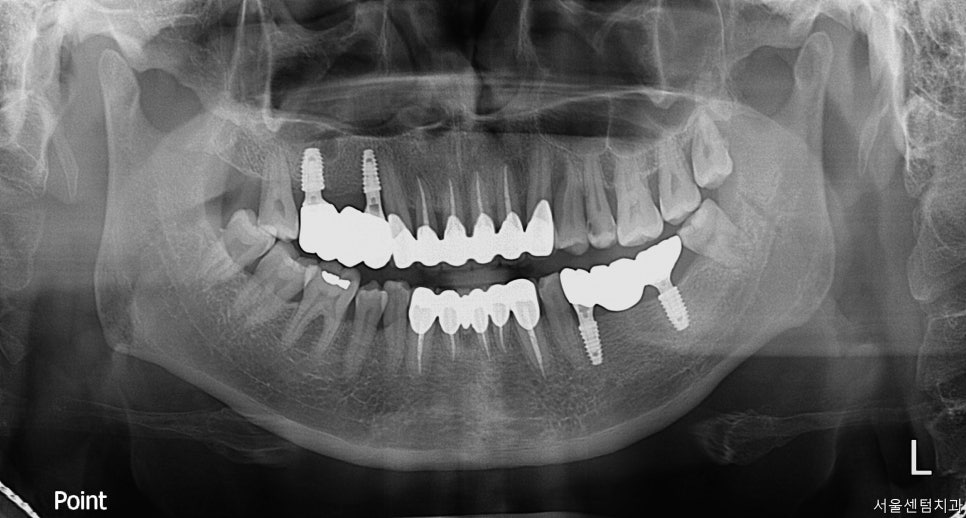

처음 오셨을 때 이미 어금니가

여러개 없는 상황이었습니다.

일단 파노라마 찍고 치근단 엑스레이

CT까지 확실히 촬영한 후 확인했습니다.

자세히 살펴보면 치석도 치아 사이사이

치간 사이에 꽤나 많은 케이스입니다.

그렇다 보니 당연히 잇몸의 건강 또한

좋은 상황은 아니었고요.

먼저 하악의 임플란트 먼저 식립을 진행하였는데요.

처음 방문하신 이후 약 10일 후에 진행하였습니다.

그 이후 상악은 한 달 뒤쯤 식립하였습니다.

상황에 따라 위에를 먼저 할지 아래를 먼저 할지

보기도 하는데 이분 같은 경우 양쪽 다

치아가 없으시다 보니 한쪽이라도 먼저

식사하실 수 있게 비교적 보철이 빨리 올라갈 수 있는

하악 어금니 수술을 먼저 진행하였습니다.